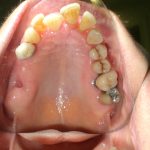

Après traitement orthodontique et réalisation d’une attelle coulée collée (courtoisie Dr Patrick Fournier)